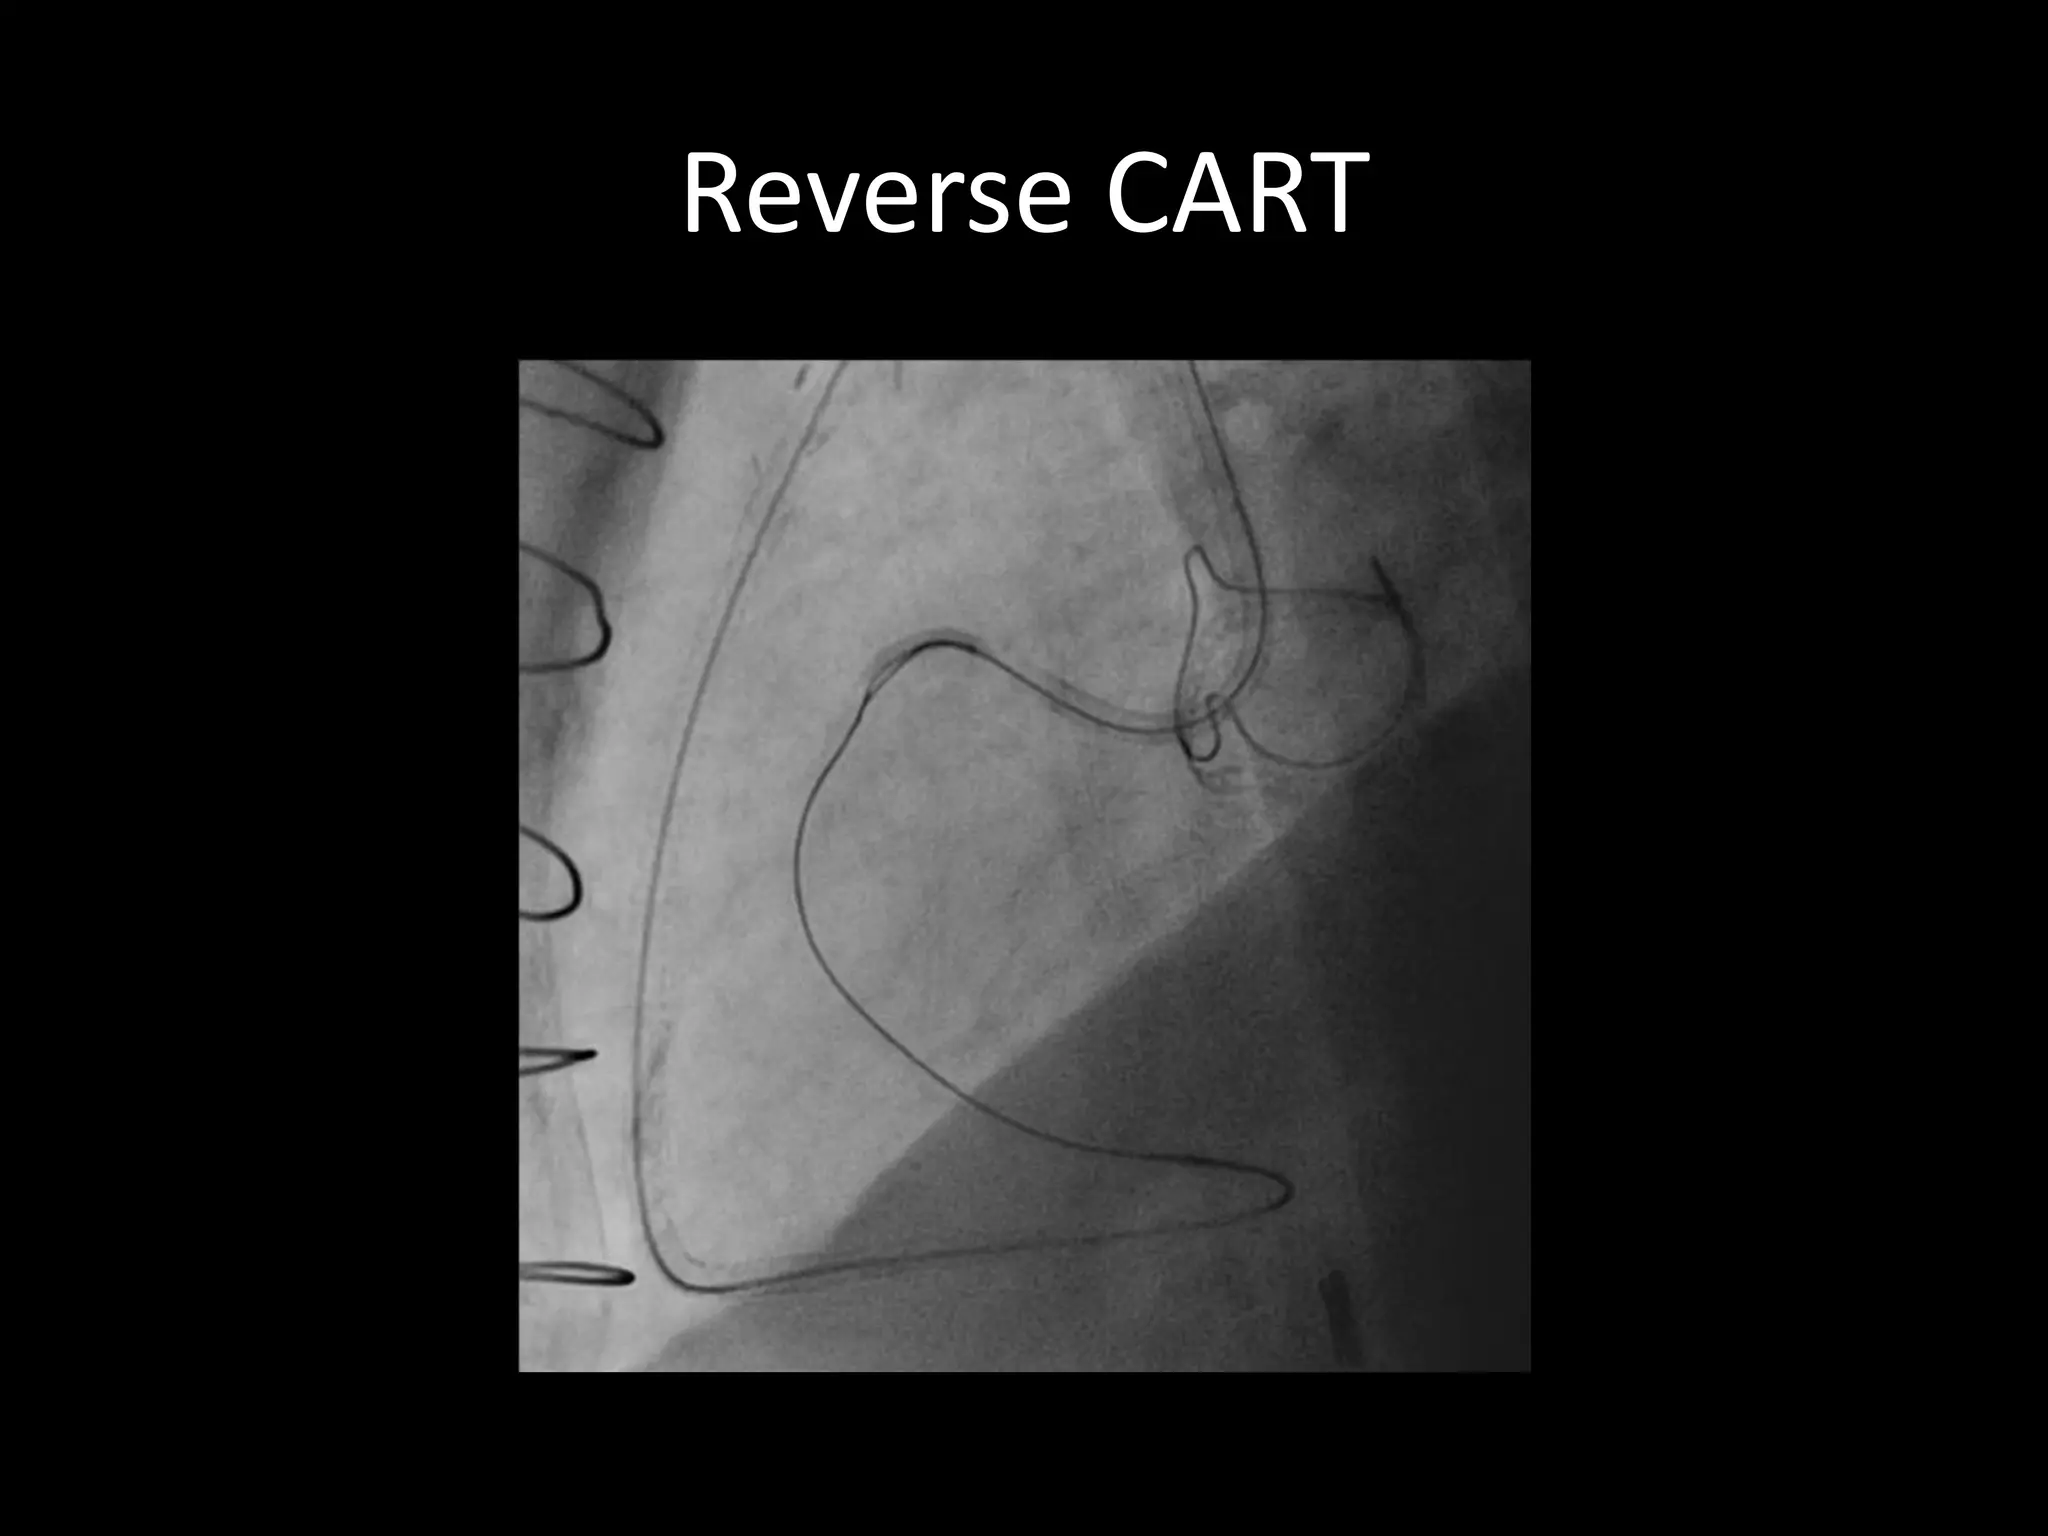

This document provides guidance on evaluating the feasibility of percutaneous coronary intervention (PCI) for a chronic total occlusion (CTO). Key factors to consider include: the patient's tolerance for a long procedure, contrast load, and radiation exposure; the CTO's proximal cap ambiguity, length, distal landing zone, and presence of interventional collaterals; and ensuring good quality angiography. With adequate planning and use of appropriate CTO techniques, feasibility is nearly always present for symptomatic patients. Success rates of CTO-PCI are reported to be 94% when using a planned approach.